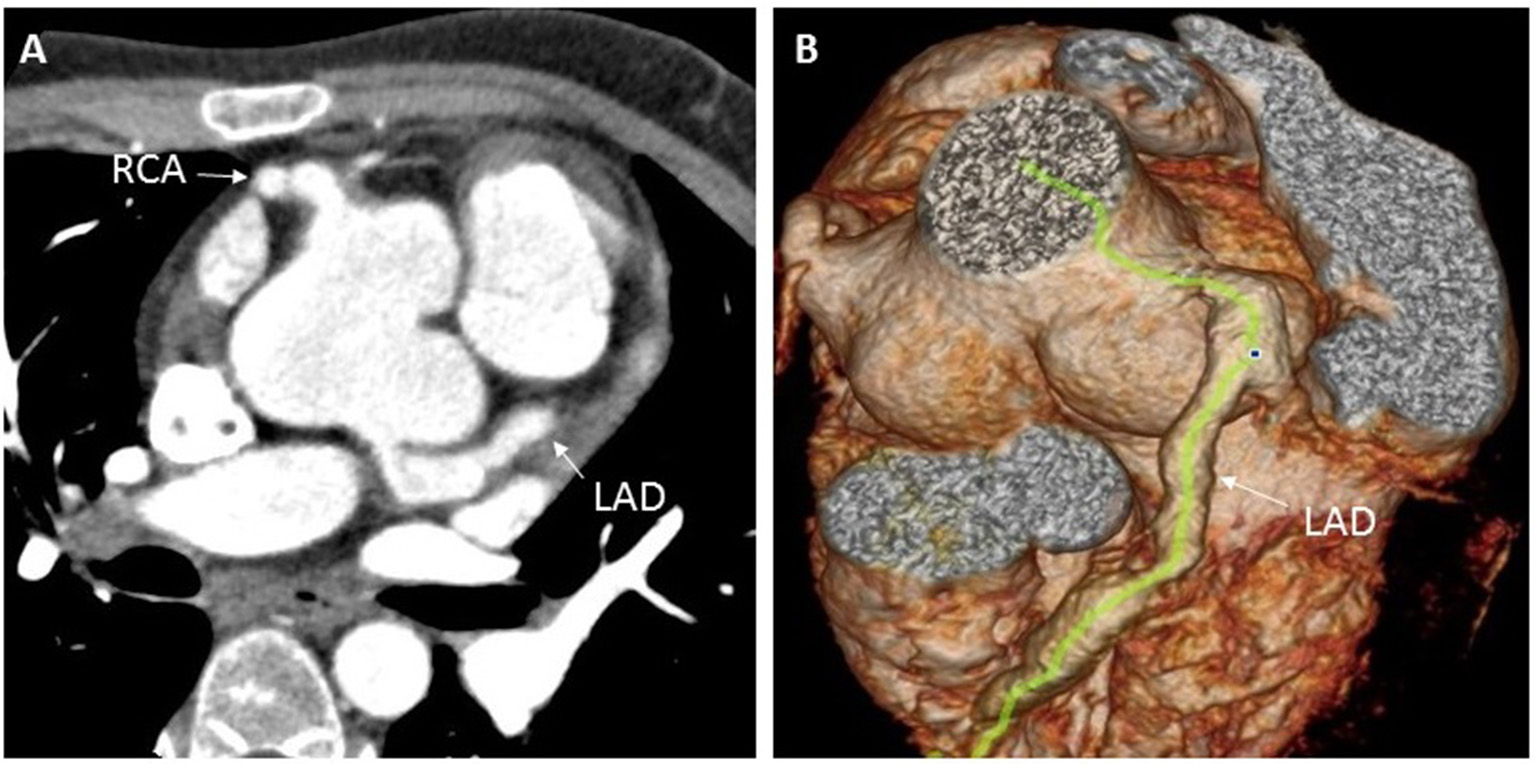

One year later, at the age of 9 years, the child was again brought to the hospital with complaints of edema and easy fatiguability on ambulation. On physical examination, significant findings including systemic edema, hepatomegaly, and a pronounced second heart sound. Laboratory results showed elevated levels of both erythrocyte sedimentation rate (70 mm/h; normal reference range: 0–30 mm/h) and N-terminal pro b-type natriuretic peptide (NT-proBNP) (1,381 pg/ml; normal reference range: 0–84 pg/ml). On echocardiography, the estimated systolic pulmonary arterial pressure (PAP; evaluated on the basis of the tricuspid regurgitation velocity), was 60 mmHg, suggestive of PAH (Figure 2). Bilateral coronary aneurysms were also detected. A general CT scan of the aorta revealed dilatation of the aortic sinus. The bilateral pulmonary and coronary arteries were also found to be dilated (Figure 3), while the abdominal aortic stem and the distal section of the superior mesenteric artery showed minor dilatation. An electrocardiogram revealed ST-segment and T-wave changes. There were no other findings suggestive of connective tissue disease, and a contrast-enhanced abdominal CT scan did not show the presence of an intrahepatic shunt. The child's family refused a right heart catheterization procedure. Therefore, the patient was diagnosed with (1) CAEBV; (2) PAH; (3) cardiac insufficiency (Class III); and (4) systemic vasculitis and managed conservatively. He was administered immunosuppressants (prednisolone 25 mg qd), the targeted pulmonary pressure-reducing drugs (sildenafil 25 mg bid and bosentan 31.25 mg bid) and antiplatelet therapy (clopidogrel 50 mg qd). The patient was also administered cyclophosphamide 4 times pulse therapy once every 2 weeks, with a cumulative 4-g dose of the drug. This combination therapy resulted in a decrease in his systolic PAP to 40 mmHg on echocardiography, and a reduction of NT-proBNP level to 62.3 pg/ml.

FIGURE 3

www.frontiersin.org

Figure 3. Enhanced coronary CT examination showing left and right coronary artery aneurysms (A), and three-dimensional CT reconstruction of the aorta showing dilation of the aortic root and the left anterior descending coronary artery (B). CT, computed tomography; LAD, left anterior descending; RCA, right coronary artery.